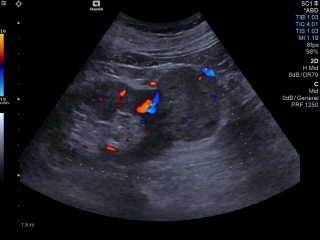

Die Ultraschalldiagnostik ist in allen Bereichen der Medizin eine der wesentlichen Säulen der bildgebenden Diagnostik und ist ein essentieller Bestandteil der täglichen Routine. Diese bildgebende Technik gehört zu der am schnellsten wachsenden Verfahren in der Medizin. Der medizinische Ultraschall, liefert in vielen Bereichen beeindruckende Fortschritte und führt zu einer Steigerung des aktuellen Wissens über moderne Diagnose- und Interventionstechniken. Für eine optimale Vorbereitung auf diesen Entwicklungstrends, Bedarfs es einer kontinuierlichen Aus- und Weiterbildung.